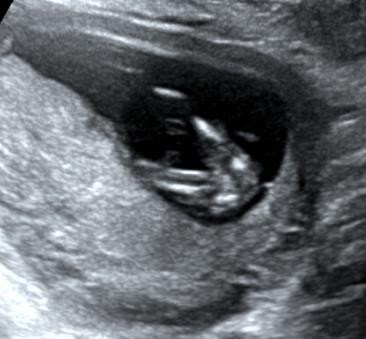

当然,这个时期我们除了重点观察TA的肢体以外,此时需要重点关注NT。

NT测量一般在11-13+6周内进行。

此时测量彩具有参考意义,但测量NT完全看宝宝的心情。

因为TA 有时候真的很不给面子。。。

有这样趴着的;